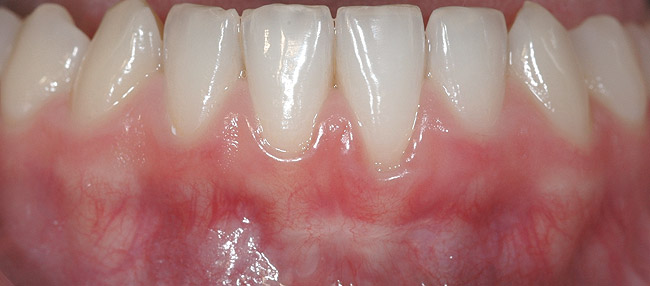

CASE 5 Fig 12. Post-orthodontic Miller Class I recession of lower left central incisor 9 months after completion of first orthodontic treatment.

Figure 12

Fig 13. Clinical view of same patient 2 years after orthodontic treatment only, showing almost complete spontaneous root coverage.

Figure 13

In Miller Class I recessions, orthodontic tooth movement alone may be sufficient. After correction of root position, spontaneous root coverage may occur, making surgical intervention superfluous (Figure 12 and Figure 13). However, if residual recession persists, the practitioner can choose either to follow up the case with SPT for 1 to 2 years, aiming for further spontaneous improvement, or proceed directly to surgical root coverage.